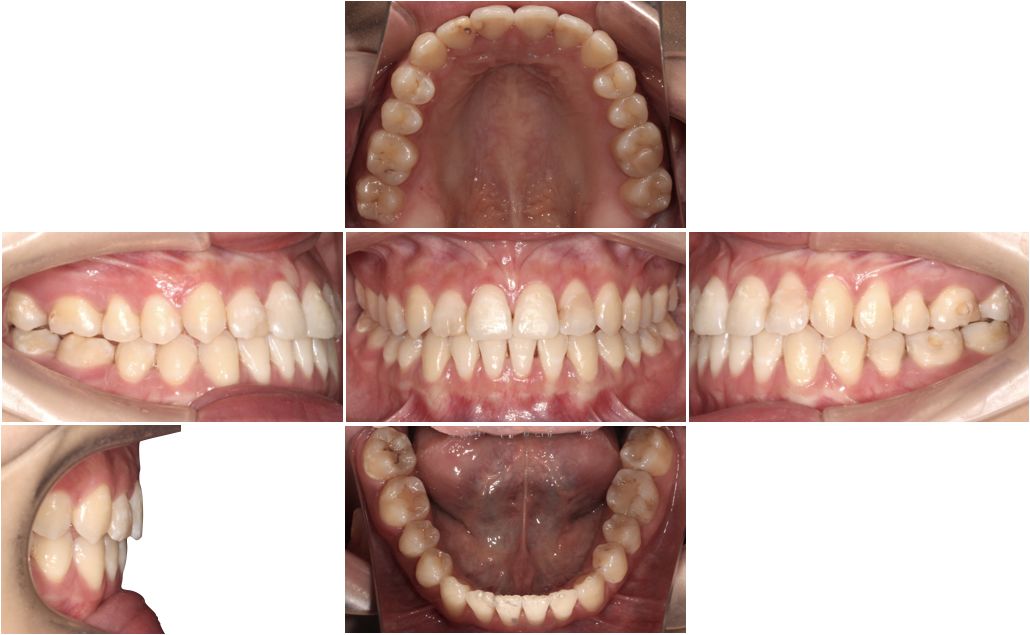

口腔检查:

上下牙弓呈方圆形;双侧尖牙、磨牙III类关系;21牙与31牙呈切合;前牙呈现约1 mm的局部开合;下颌中线较上颌中线左偏1 mm。

模型分析:

上颌拥挤度:1.5 mm,下颌拥挤度:1.5 mm。Bolton指数:全牙比为86.70%,前牙比为75.5%。患者上下颌牙列均存在前牙段轻度的拥挤,前牙和全牙的bolton指数均偏小,提示上颌牙齿牙冠宽度偏大。